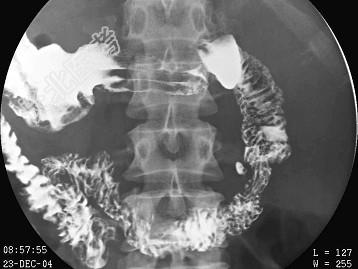

单项选择题女,46岁, 排便困难,结合图像, 最可能的诊断为 ( )

A、正常肠圈

B、球部溃疡

C、球部憩室

D、降段憩室

E、水平段憩室